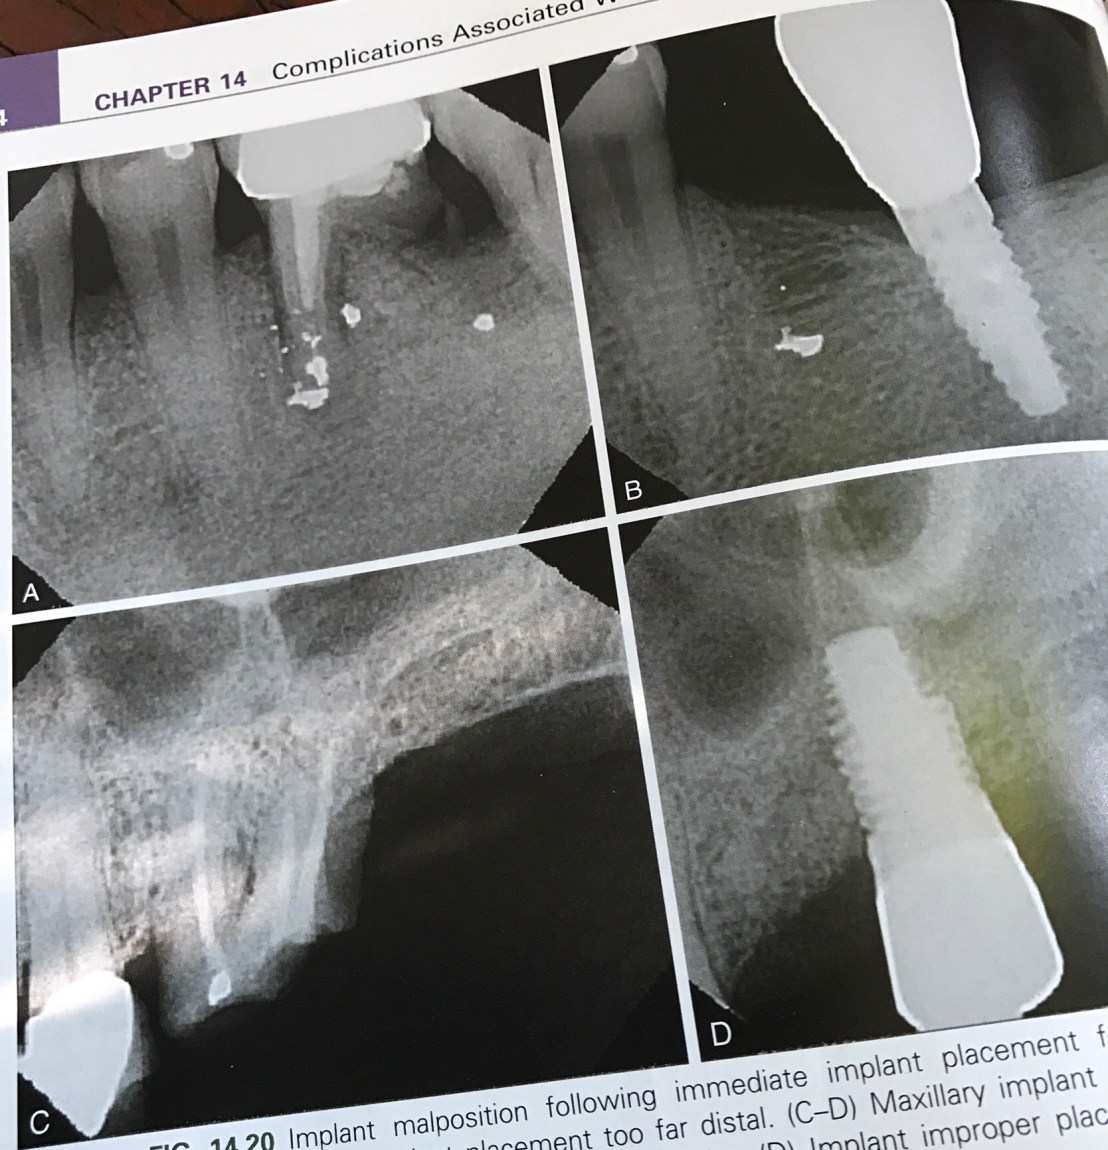

แสดงความผิดพลาดในการวางตำแหน่ง จะเห็นได้ว่า แม้จะมี socket ถอนฟันเป็นตัว guide แต่ตำแหน่งที่ฝังยังออกไป Distal มาก

ดังนั้นการใช้ข้อมูลจาก X-ray + Surgical stent จึงยังเป็นสิ่งจำเป็นอยู่ แม้ในเคส Immediate ก็ตาม